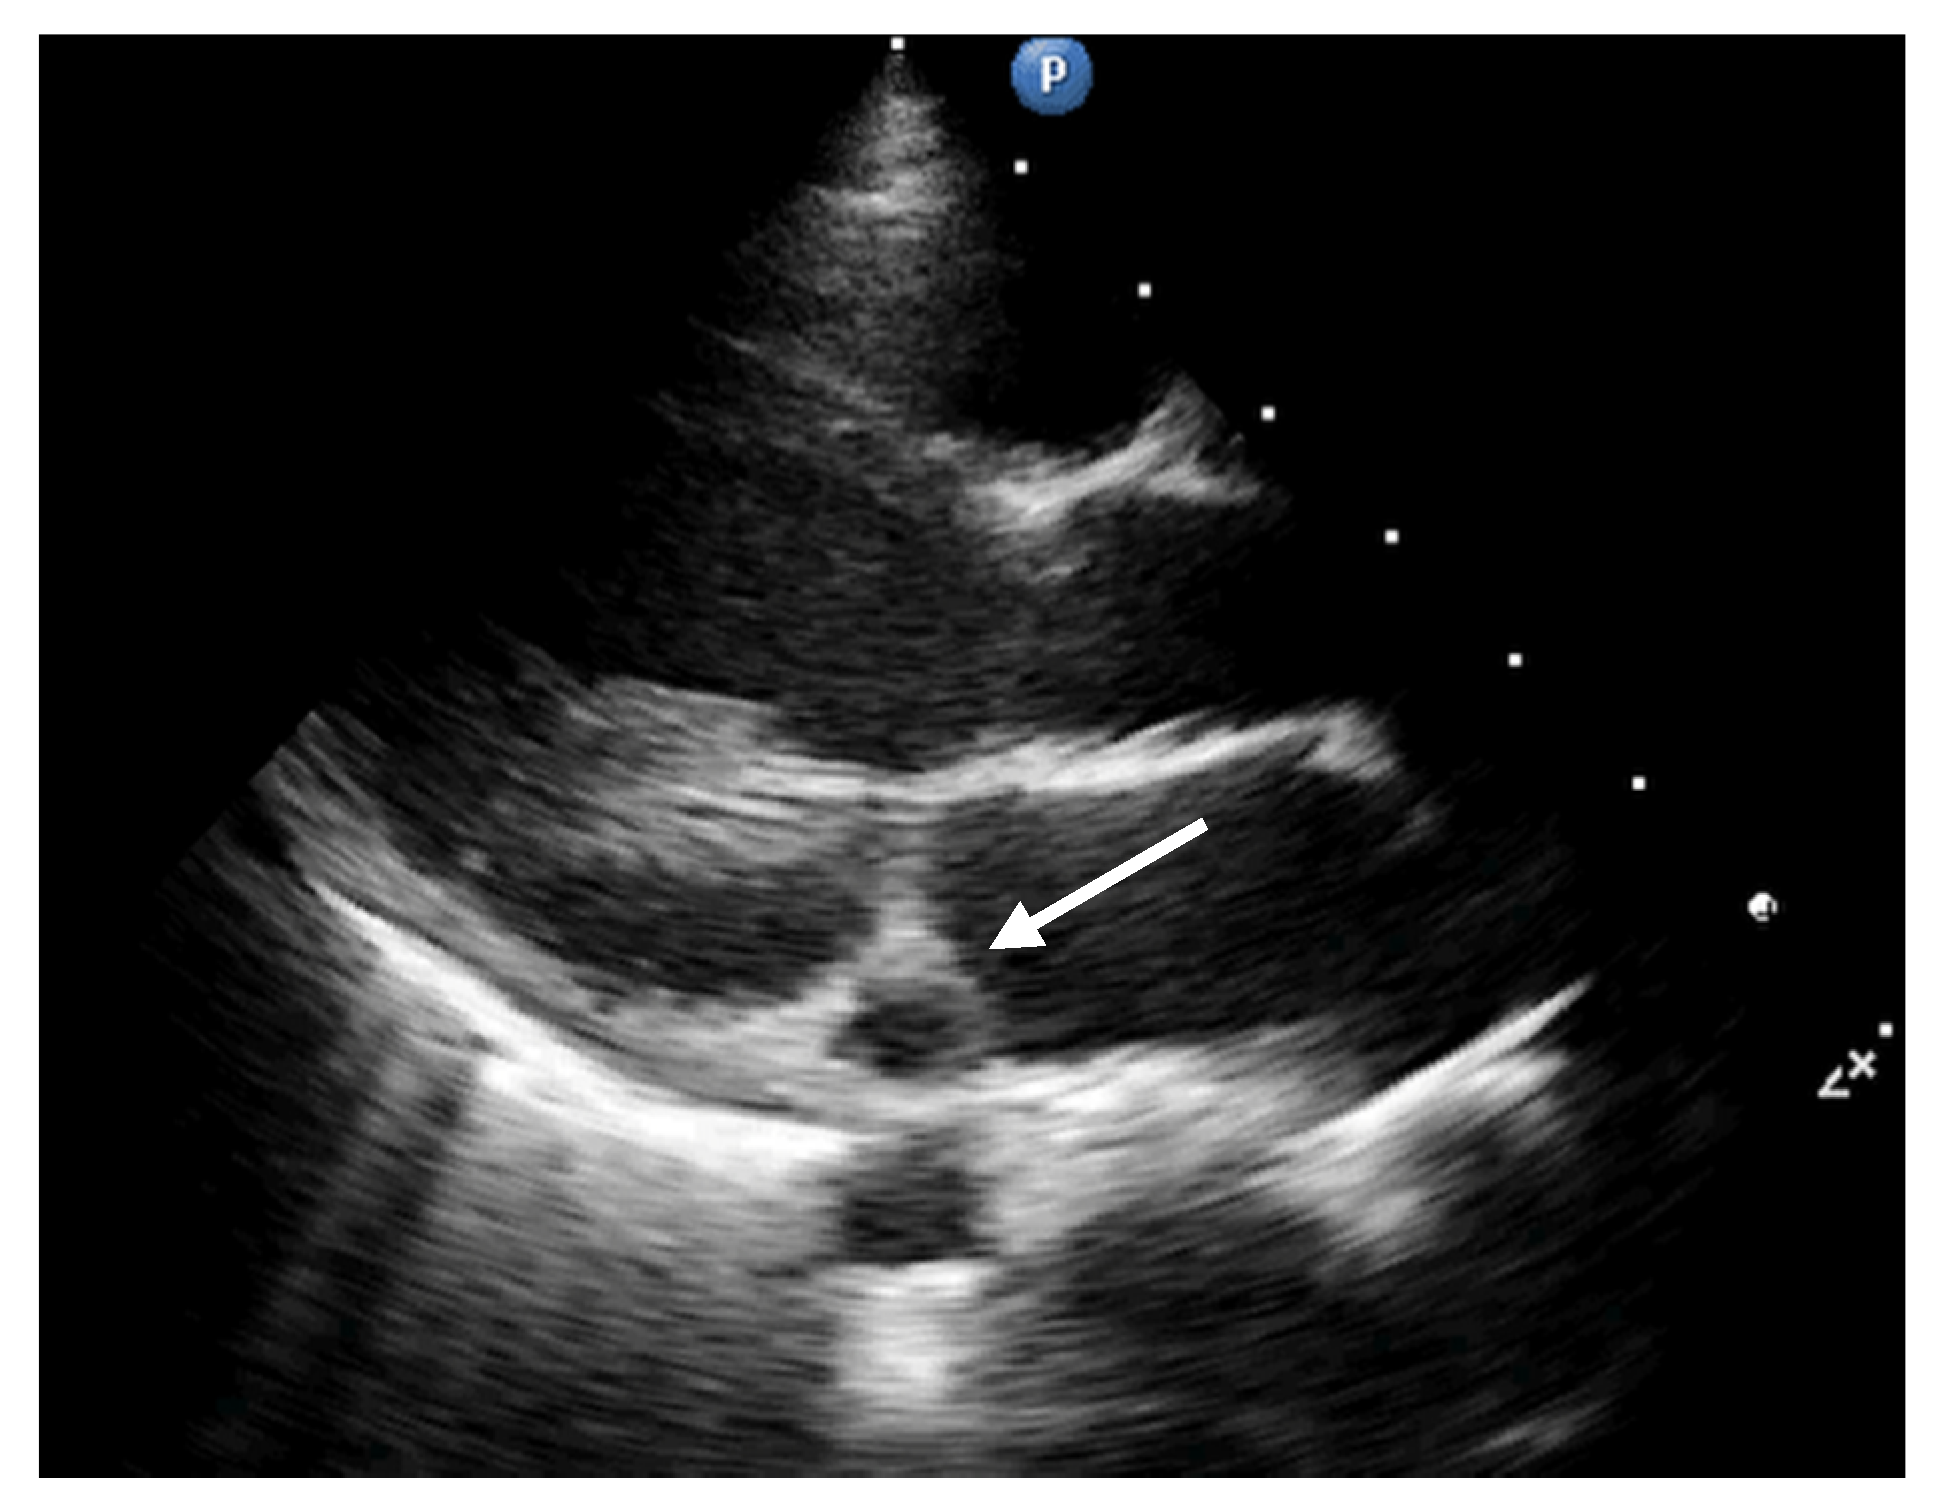

2. Case Report